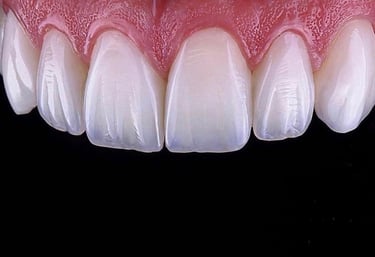

Veneers

Transform your smile with dental veneers—thin, custom-made layers that cover the front surface of your teeth.

At Dr. Teeth, we specialize in composite veneers and ceramic veneers, which are ideal for correcting:

Veneers provide a natural look, minimal invasiveness, and long-lasting aesthetics—perfect for anyone who wants a radiant Hollywood smile.